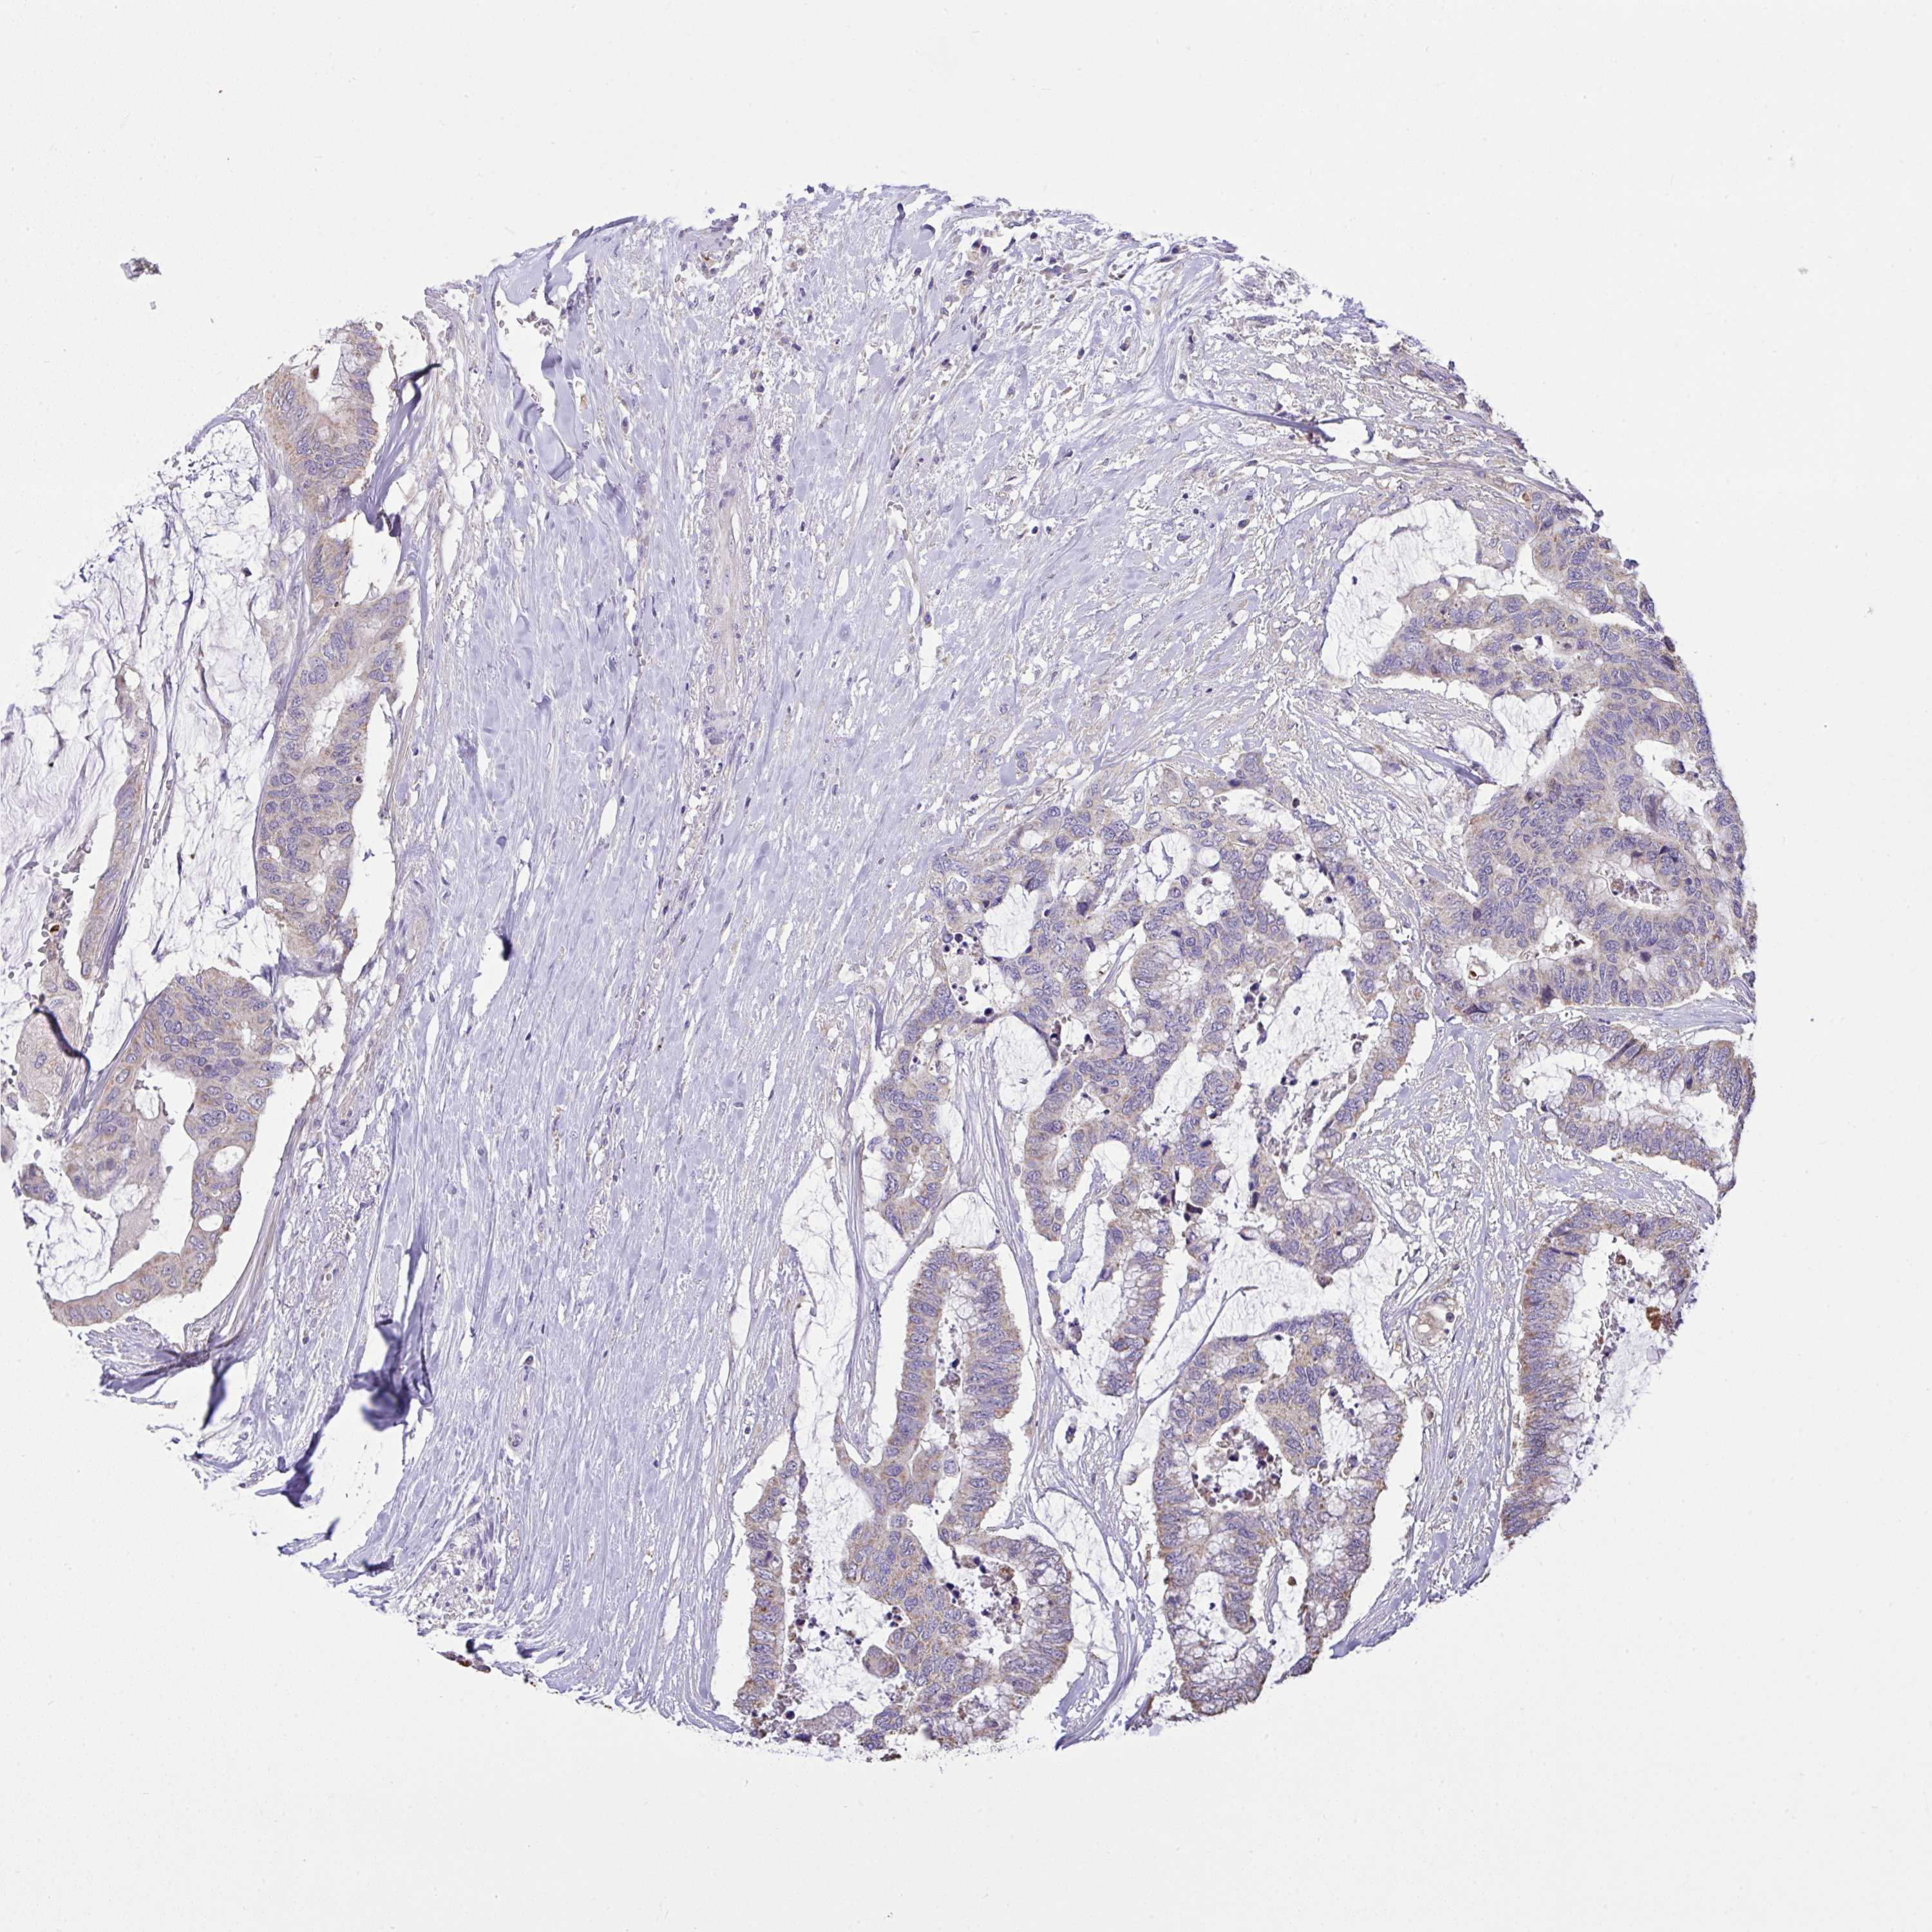

CANCER COLORECTAL CANCER Show tissue menu

Colorectal cancer

Human cancer